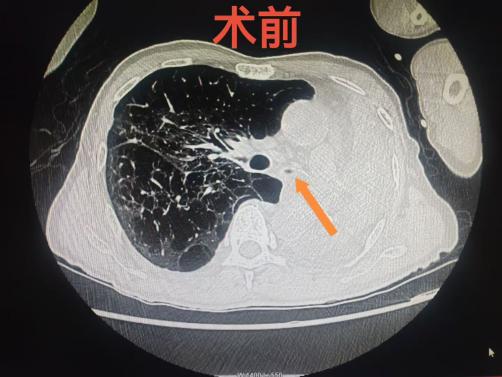

该患者持续咳嗽、咳痰、活动后气促4年多时间,近期因症状加重并出现咯血20天入院,既往有陈旧性肺结核史。经检查发现,患者左主支气管被肿瘤完全堵塞,导致左肺无法通气,一度严重缺氧,生命垂危。由于老人年事已高,肺功能极差,且合并感染及呼吸衰竭等复杂情况,传统外科手术风险极高,无法实施。面对这一难题,呼吸与危重症医学科迅速联合麻醉科、重症医学科、肿瘤科、心脏大血管外科、影像科等多个科室团队进行MDT会诊,最终决定为老人施行微创的硬质支气管镜联合软质支气管镜支架植入术。

术中,手术团队先置入硬质支气管镜,在确保患者持续通气安全的前提下,再联合软质支气管镜精准定位,成功在堵塞的左主支气管内放置了一枚支架,瞬间打开了“生命通道”。术后,患者呼吸困难立即缓解,缺氧状况显著改善,左肺重新复张,第二天便转回普通病房,为后续抗肿瘤治疗赢得了宝贵时机。